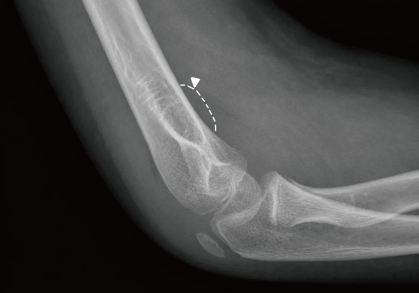

A 13 year-old boy presented with fever and not swollen discomfort of the right elbow without swelling and tenderness. Four months previously, he had been diagnosed to have Ewing sarcoma of the right ilium and had undergone five cycles of preoperative chemotherapy. He had contracted a C. tropicalis urinary tract infection during a febrile neutropenia episode after chemotherapy, which was treated with itraconazole and broad spectrum antibiotics for 7 days. No growth was reported in the last urine culture after itraconazole treatment. Recently, he had been on preoperative chemotherapy (vincristine, ifosfamide, doxorubicin, and etoposide), which he had completed 9 days prior to presentation.At presentation, his body temperature was 37.5℃, pulse rate 120 per minute, respiration rate 20 per minute, and blood pressure 130/70 mmHg. physical examination revealed a slight throat infection, but no sinus tenderness, nor tonsilar nor lymph node enlargement. Heart and lung sounds were normal, liver and spleen were non-palpable, and no edema or pain was found in the lower extremities. He complained of discomfort of the right elbow. Laboratory tests revealed pancytopenia, and complete blood count findings were leukocytes 160/mm3, absolute neutrophil count 40/mm3, hemoglobin 9.4 g/dL, and platelet count 8,000/mm3. Broad-spectrum antibiotics (piperacilin/tazobactam and isepacin) were immediately administered after obtaining blood and urine for culture studies.After two days of antibiotic treatment, mild tenderness and swelling (without heating sensation) were detected on the right elbow. A simple radiograph obtained on the 3rd hospital day revealed soft tissue swelling with a positive fat pad sign (Fig. 1). Ultrasonography on the 4th hospital day showed soft tissue edema and articular effusion, and subsequently, 15 mL of yellowish fluid was aspirated from the joint and cultured (Fig. 2). A three phase bone scan (Fig. 3) performed on the 6th hospital day for the differential diagnosis of tumor metastasis and infection showed a limited region of uptake on the right elbow, suggesting the possibility of arthritis.The symptoms and signs of arthritis aggravated despite a 10-day course of broad-spectrum antibiotics. On the 11th hospital day, cultures of synovial fluid and tissue demonstrated the presence of C. tropicalis. However, blood and urine culture specimens were negative. Follow-up right upper elbow ultrasonography on the 11th hospital day showed elbow articular space effusion and hypertrophic synovium. Emergent decompression was performed on the same day, and a drain tube was placed in the right elbow articular space. During the operation, 2 mL of a yellowish-red turbid synovial fluid sample was obtained and submitted for culture, which later confirmed the presence of C. tropicalis. In addition, abdominal computed tomography on the same day showed no evidence of hepato-splenic candidiasis.Intraveneous itraconazole 400 mg/day (5 mg/kg/day) was started on the 11th and 12th days. Intravenous itraconazole was decreased to 200 mg/day on the 13th day and then kept at the same dose. Fever, joint swelling, and arthralgia gradually resolved after itraconazole treatment, and after 2 weeks of intravenous itraconazole treatment on the 25th hospital day. Intravenous itraconazole 200 mg/day was substituted for oral itraconazole solution at 200 mg/day.The antifungal treatment was maintained for three months, and from 14 days after treatment commencement the patient had no elbow pain and was without disability. Furthermore, no relapse of the fungal arthritis occurred during oral itraconazole therapy. Simple radiography and a bone scan carried out after 3 months of antifungal treatment showed no abnormal lesion related to septic arthritis, and oral itraconazole was discontinued.

Fig. 1

Lateral view of the right elbow shows soft tissue swelling with a positive fat pad sign (arrow head).